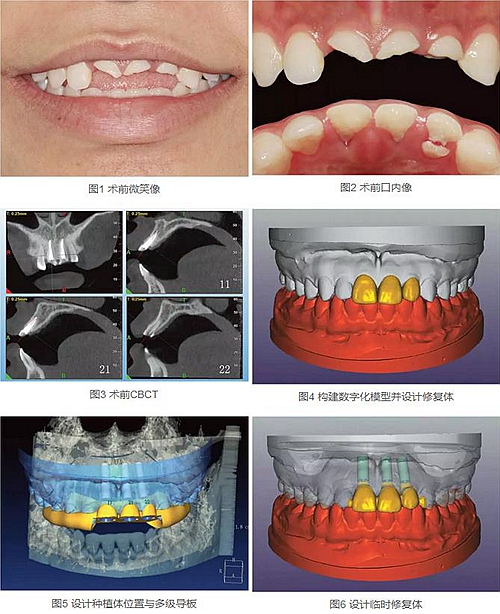

23歲女性患者,外傷導致上前牙折斷3天。檢查:中微笑線;上頜右側(cè)中切牙至左側(cè)側(cè)切牙殘根,不松動,腭側(cè)缺損達齦下5mm,牙齦中等厚度,齦緣基本完好。CBCT顯示:根長約11mm,牙根長軸與牙槽突方向基本一致,唇側(cè)骨板完好、厚度1.0mm,可用骨高度21mm。全身情況良好。

拍攝臨床照片、拍攝輕開口位CBCT(NewTom)、取聚醚印模灌制超硬石膏模型。

構(gòu)建數(shù)字化模型并設(shè)計修復體:將超硬石膏模型在口外掃描(Identica Hybrid),獲取軟硬組織表面形態(tài),構(gòu)建數(shù)字化模型,確認咬合情況。根據(jù)天然牙殘根頸部形態(tài)設(shè)計修復體頸部形態(tài),使修復體頸緣輪廓與原有天然牙一致;按正常牙弓弧度與覆、覆蓋關(guān)系,結(jié)合紅白美學等原則確定修復體的三維形態(tài)。最后,導入患者面部照片,確認模擬修復效果。

設(shè)計種植體位置并制作多級導板:利用Segma設(shè)計軟件,將CBCT數(shù)據(jù)和模型掃描數(shù)據(jù)進行配準,調(diào)入模擬修復效果數(shù)據(jù),以修復為導向設(shè)計種植方案,設(shè)計種植體螺絲孔開口從修復體舌窩處穿出,最終實現(xiàn)螺絲固位的一體化基臺冠修復。根據(jù)種植體信息設(shè)計多級導板,參考修復體形態(tài)設(shè)計導板植入?yún)^(qū)頸緣外形,打印生成種植導板(Segma),并安裝金屬引導環(huán)。

設(shè)計并制作臨時修復體:如前所述,按照美學效果和咬合關(guān)系設(shè)計臨時冠外形,頸部形態(tài)與模型齦緣輪廓一致,保證臨時修復體在術(shù)后可以封閉拔牙窩。3顆臨時冠為連冠,齦外展隙適當加大,為術(shù)后軟組織生長提供一定的空間。在臨時冠近兩側(cè)鄰牙的切角處預留翼板,保證臨時冠戴入時可以找到準確的位置。以銑削的方式加工臨時冠(Segma),待種植體植入后將其在口內(nèi)粘接于臨時基臺上。